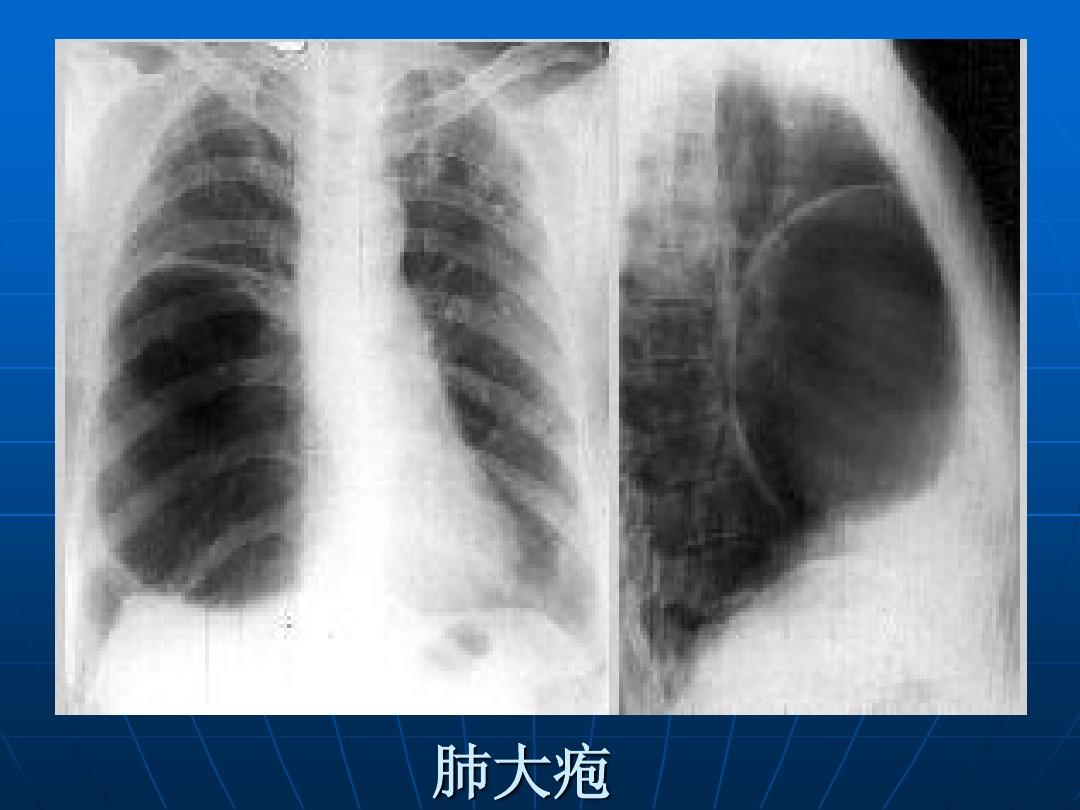

肺大泡x线

肺大泡x线,

肺大疱出现胸闷气短建议及时就医,轻者对症治疗,重者需手术治疗

一图看懂什么是肺大疱

肺大疱x线